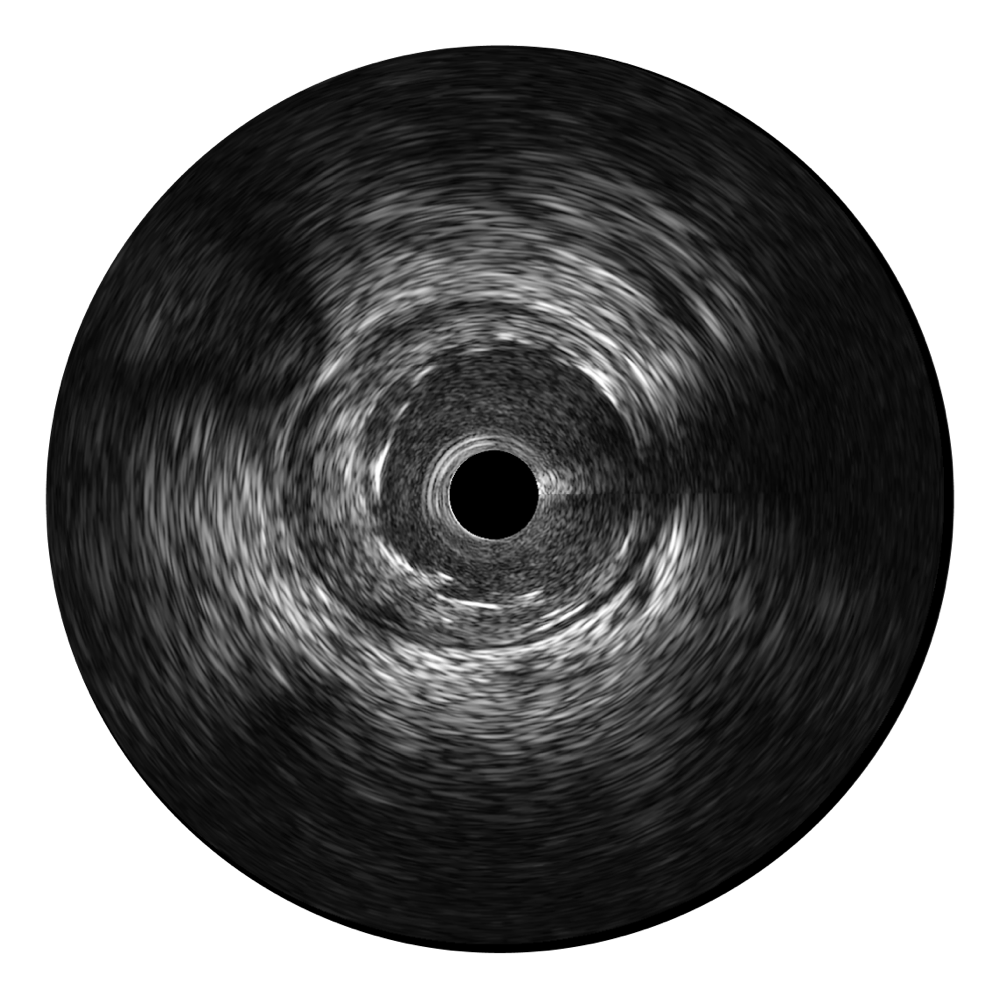

米兰官方网站宽频IVUS图像

对比传统IVUS导管成像,米兰官方网站宽频IVUS图像的近场支架梁显影更细腻,远场中膜外血管仍清晰可辨,兼顾远中近,兼顾分辨力与穿透深度